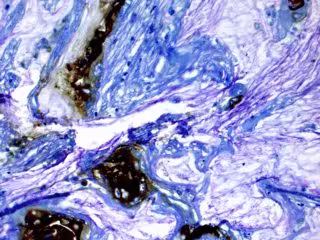

Los científicos del Laboratorio Cold Spring Harbor (CSHL), en Estados Unidos, han descubierto que pueden detener el crecimiento de las células de cáncer de páncreas al interferir con la forma en que las células almacenan el colesterol. Sus hallazgos en ratones y modelos de páncreas cultivados en laboratorio apuntan hacia una nueva estrategia para tratar la enfermedad mortal.

El estudio, publicado en el 'Journal of Experimental Medicine', fue dirigido por el profesor de CSHL David Tuveson. El equipo de Tuveson quería saber por qué las células cancerosas pancreáticas, como muchas células cancerosas, producen cantidades abundantes de colesterol.

El colesterol es un componente esencial de las membranas celulares, pero el equipo de investigación determinó que las células cancerosas pancreáticas producen mucho más de lo que necesitan para apoyar su propio crecimiento.

Las células cancerosas del páncreas parecen prosperar gracias a esta síntesis hiperactiva de colesterol. El equipo cree que esto es probablemente porque están aprovechando otras moléculas generadas por la misma vía. Son capaces de mantener la vía en funcionamiento y mantener su suministro gracias a una enzima llamada O-actiltransferasa 1 (SOAT1) del esterol, que convierte el colesterol libre en su forma almacenada y que las células cancerosas del páncreas tienen en abundancia.

Cuando los investigadores eliminaron la enzima SOAT1 mediante manipulación genética, evitando que las células convirtieran y almacenaran su colesterol, las células cancerosas dejaron de proliferar. En los experimentos con animales, la eliminación de la enzima detuvo el crecimiento del tumor.